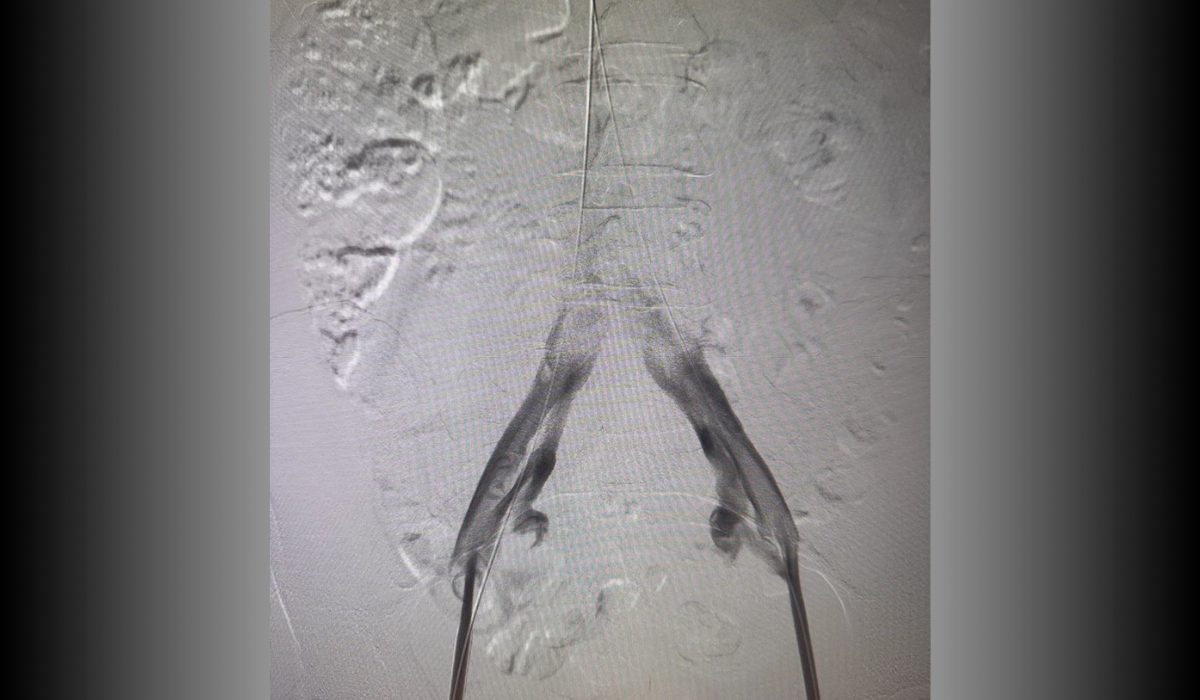

Post-treatment: Endovascular reconstruction with stent placement

Post-treatment

Endovascular reconstruction with stent placement. Restoration of venous flow with symptom resolution.